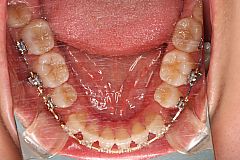

下顎前突治療例7(下顎左右側第一小臼歯、唇側の矯正装置)

骨格性下顎前突症。下顎歯列弓が上顎歯列弓に対して小臼歯1歯分前方位にある。上顎中切歯間に僅かな空隙を認めます。

外科矯正治療も考慮される症状でしたが、患者様が手術を望んでおらず、また、矯正治療単独でも咬合の改善は可能と判断し、下顎両側の第一小臼歯を抜歯して骨格的な問題をカムフラージュすることにしました。

マルチブラケット矯正装置(ピーチゴールドワイヤー)

本症例は小臼歯1歯分下顎歯列弓が上顎歯列弓に対して前方位にあります。小臼歯1歯分以上の前方位になると下顎小臼歯を2本抜歯しなければならないため通常は外科手術を併用した矯正治療を選択することが多くなります。

本症例は外科矯正とのボーダーラインケースといえます。顎間ゴムの使用状況や口腔衛生状況など、患者様の協力も良好で2年を予定していた治療期間も1年5か月で済みました。